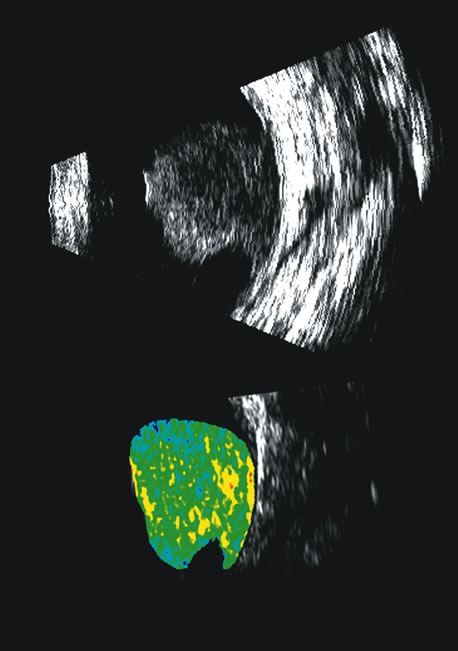

The representation of volume and three-dimensional perspectives of the diseased vitreous, retinal detachment, choroidal detachment, and tumors can add to presurgical conceptualization and is critical to characterization of tumors in relation to prediction of lethality.45 In addition, volume measurement of the choroid permits studies of both surgical and physiologic rates of clearance of hemorrhage, whereas vitreous volume studies can make the estimation of gas or other vitreous substitutes for replacement more accurate (Fig. 25).

Fig. 25. A 3D reconstruction of serial scans of a posterior pole melanoma taken with a 10 MHz transducer (left) shows the extent and relative asymmetry of the tumor within the vitreous cavity. 3D biometry can be useful for treatment planning for radiotherapy and brachytherapy. 3D reconstructions of 50 MHz serial ultrasound scans and parameter images of a melanoma involving the ciliary body and anterior uvea (center, right) before and after treatment with combined ultrasound hyperthermia and brachytherapy. Changes in the concentration of ultrasound scattering elements related to tissue necrosis are seen as color scale in the pre- and postimage region of the tumor shifts, from blue, indicating relatively low acoustic concentration, to yellow and green, indicating higher concentrations of scatterers.